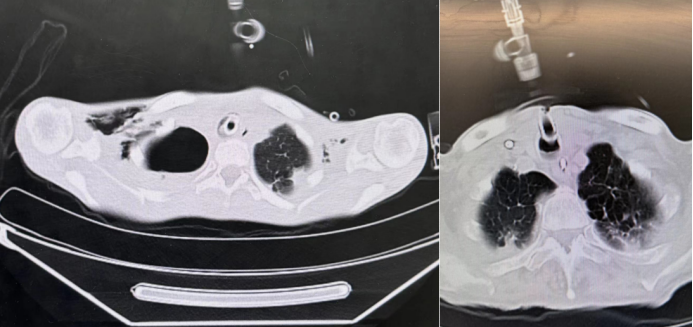

通过CT可观察到气囊上区域的高密度影与液平(图1),超声检查也可直观评估滞留物的存在和量(图2),为临床干预提供影像学依据。

图片

1  CT下观察气囊上滞留物

2  超声评估气囊上滞留物